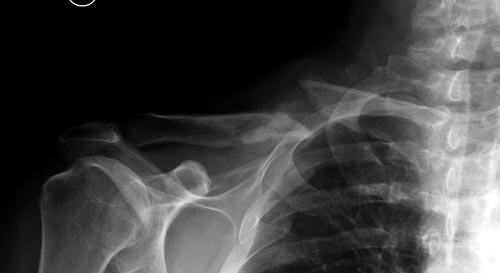

Болезненные ложные суставы надо оперировать, и здесь представлен случай

свежего болезненного ложного сустава, оперированного через 4 месяца.

Освобожден средний фрагмент и боковая компрессия лагированием, фиксация

пластиной..

Вложение не в текстовом формате было извлечено…

Имя     : Clavicle 3 one month.jpg

Тип     : image/jpeg

Размер  : 30173 байтов

Описание: отсутствует

Url     : http://weborto.net:8080/pipermail/ortho/attachments/20141124/0ee515fb/attachment-0035.jpg